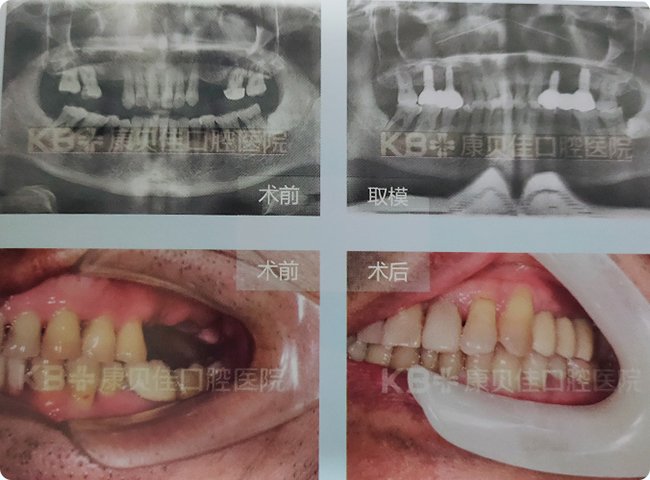

许先生 55岁

由于刷牙方法不正确导致牙根外露后没有引起重视,最后上颌共缺失6颗牙,到医院检查后发现牙槽骨高度不够、宽度也不够,不能做常规种植。 康贝佳口腔种植专家为其定制了上颌窦外提升的同时植入种植体的方案,术后效果非常满意。

治疗方案:

上颌 种植4颗恢复6颗